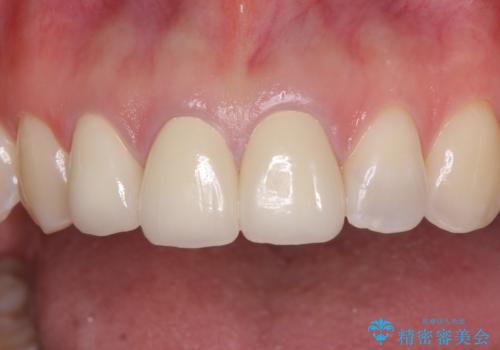

前歯の審美歯科治療 オールセラミッククラウンと部分矯正

- 上の前歯のセラミッククラウンが古くなったことと、下の前歯のデコボコを気にして来院された患者様です。

前歯は一部根管治療を行った後にオールセラミッククラウンに補綴することとしました。

当初は上顎の補綴治療のみを希望されていましたが、仮歯装着期間に上下の前歯の接触が気になったため、部分矯正を行うこととしました。

審美面と合わせて機能面も改善され、患者様には大変満足していただきました。